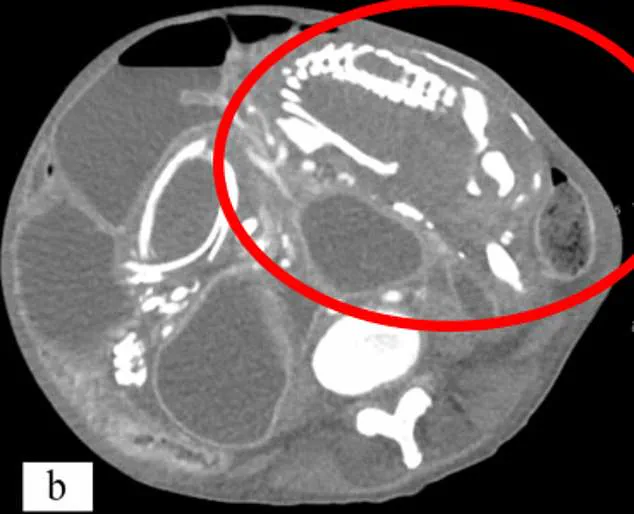

The process begins with an ectopic pregnancy, a condition where the embryo implants outside the uterus. Around 1 in 11,000 pregnancies fall into this category, and while most ectopic pregnancies occur in the fallopian tubes, some develop in the abdomen, ovaries, or even at the site of a previous C-section scar. When these pregnancies fail, the maternal body typically reabsorbs the tissue. However, if the fetus is more than 12 weeks old, its skeletal structure—which now contains bone—becomes too large to be absorbed. The immune system then encases the dead fetus in calcium, a form of biological mummification, creating a 'stone baby' that can remain in the body for decades.

The consequences of lithopedion extend far beyond the physical. Cases where the condition goes unnoticed for years often result in severe symptoms, including chronic abdominal pain, gastrointestinal issues, or even pelvic infections. In extreme cases, the mass can compress vital organs, leading to malnutrition, intestinal blockages, or cardiac arrhythmias. One tragic example involved a 50-year-old woman from the Congo who carried a lithopedion for nearly nine years before her death in 2023. Misdiagnosed and believing her condition to be a curse, she refused treatment until her body could no longer sustain her.